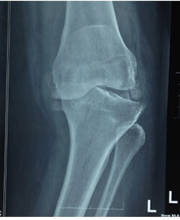

Eight Facts about Primary Knee Replacement

23 Mar 2021- It also means resurfacing. The worn-out cartilage surface is removed and lined with smooth metal, ceramic or poly materials.

- The Main indication is severe pain due to rough Cartilage, which has not improved with medication, physiotherapy.

- Osteoarthritis and Rheumatoid Arthritis are common causes.